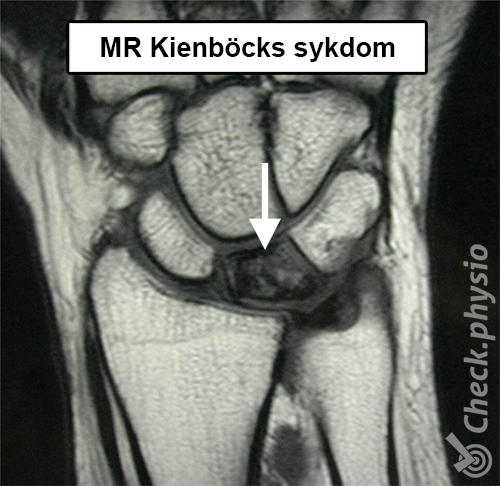

Kienböcks sykdom Lunatomalasi / avaskulær nekrose av os lunatum / død i det måneformede håndrotsbenet

Håndleddet består av åtte håndrotsben. Midt iblant disse ligger et måneformet ben som heter os lunatum. Dette benet har en viktig posisjon mellom de andre håndrotsbenene. Et annet navn for Kienböcks sykdom er lunatomalasi.

I tidlig stadium vises ofte ikke noen avvik på røntgen. Da kan en MR gi mer klarhet. I senere stadier er forandringer i os lunatum synlige på røntgen.